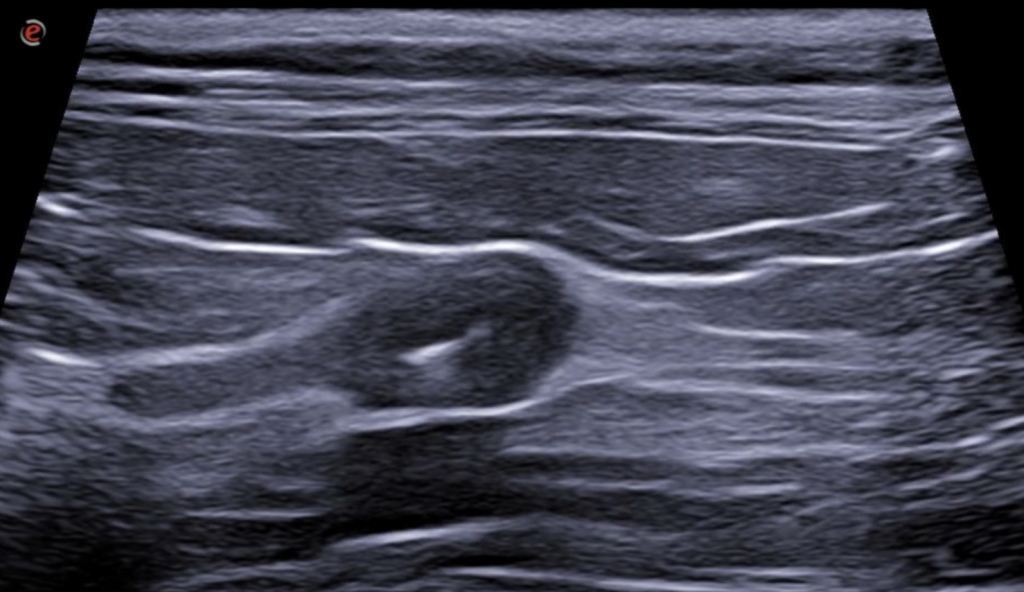

- El ureter izquierdo está ligeramente distendido y presenta en todo su recorrido la pared engrosada, observándose aproximadamente a 4 cm de su inicio, una engrosamiento marcado de su pared de forma concéntrica y circunferencial, observándose una pared hipoecogénica de 2 mm de grosor. En su interior, hay una estructura similar a la descrito en ambos riñones (cálculo), de 1.7 mm de diámetro. El ureter distalmente disminuye abruptamente de tamaño y se continúa de forma normal hasta la unión ureterovesical. El peritoneo de alrededor del ureter se aprecia hiperecogénico en todo su recorrido.